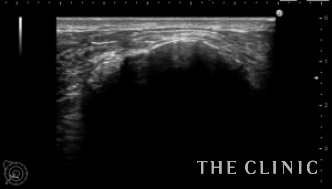

エコー所見です。

触診では左右に1個づつの7㎝大のしこりを触れましたが、エコーではさらに左に2つの石灰化したしこりを認めました。